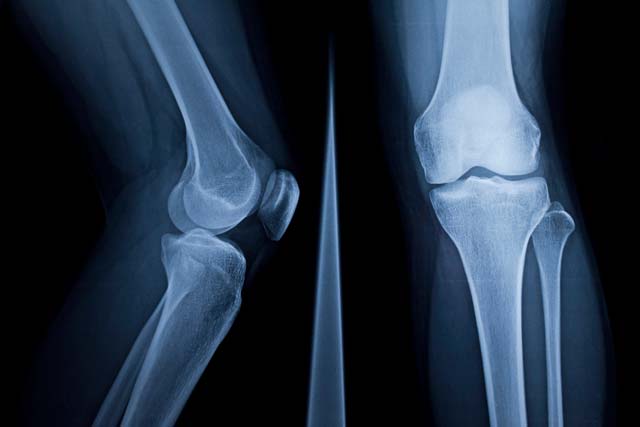

Limb reconstruction is a subspecialty of orthopaedic surgery. Reconstruction techniques are used in the treatment of limb lengthening and/or deformity correction.

These may include internal fixation, such as plating or nailing, or external fixation such as Ilizarov or Monotube frames.